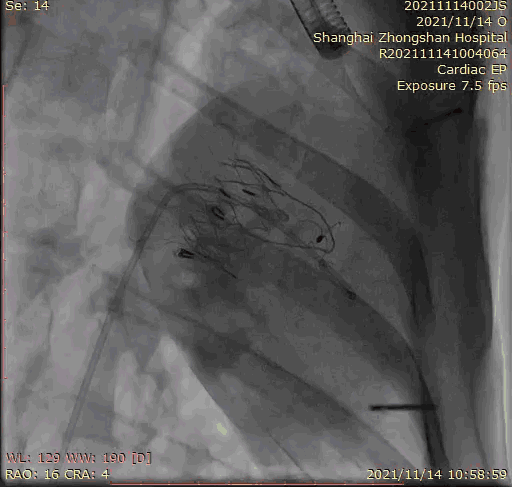

上海中山醫(yī)院葛均波院士、錢菊英院長、周達新教授、潘文志教授、潘翠珍教授、李偉教授共同完成此次臨床前研究。術(shù)后葛均波院士對Lux-Valve Plus的器械操作性能給予了高度評價,DSA和超聲影像也顯示出在本次研究中Lux-Valve Plus的安全性和有效性俱佳。

本次臨床前研究經(jīng)右側(cè)頸靜脈置入LuX-Valve Plus輸送系統(tǒng)可調(diào)彎鞘管,在DSA及超聲引導(dǎo)下將人工三尖瓣瓣膜植入到原有三尖瓣位置,利用獨特的錨定技術(shù)將人工瓣膜支架可靠固定在預(yù)定的位置。